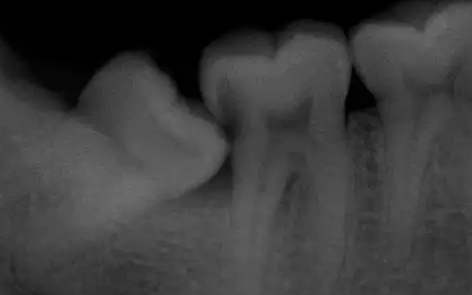

阻生智齿尽头牙图片